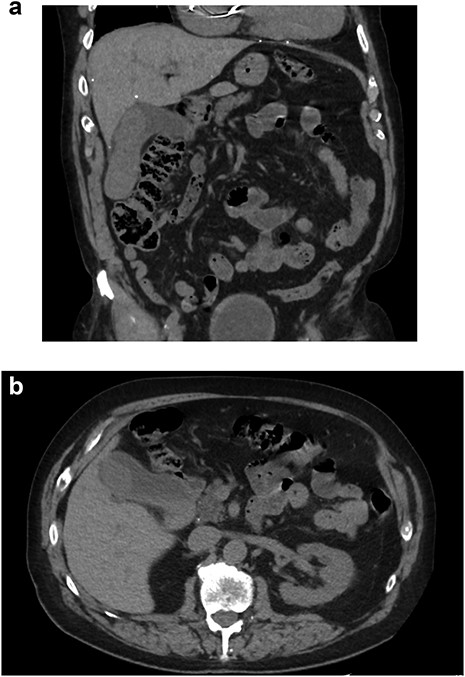

Upon further discussion, the patient reported a history of cutaneous scalp melanoma excision several years prior to his admission. The patient was established with a medical oncologist and underwent positron emission tomography (PET) CT (Fig. 3), with focal uptake seen in the right hepatic lobe adjacent to the gallbladder fossa, concerning for residual disease versus postoperative changes. MR head was performed without evidence of intracranial metastasis. Repeat CT 5 months after resection was without evidence of progressive metastatic disease. This case was presented at an interdisciplinary tumor board conference; the consensus treatment plan was to pursue single-agent immunotherapy.

PET/CT. (A) Coronal and (B) axial slices depicting change status post cholecystectomy and focal uptake in the right hepatic lobe adjacent to the gallbladder fossa